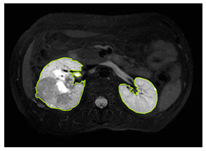

3.2.1. ROI Dataset

The images used in the study include different anatomical areas, such as the liver, spleen, and intestine. However, in order to process the data more quickly and provide more accurate results from the analysis, only the kidney areas (Regions of Interest, ROI) were extracted and evaluated. The Roboflow platform was used for spatial matching and segmentation of the kidneys. Polygonal ROI regions were defined by applying the semantic segmentation method, and then the transformations performed were verified by the radiologist, increasing the reliability of the system. In our study, MRI phase images were acquired at a resolution of 512 × 512 and the renal region of interest (ROI) was segmented and resized to 224 × 224 for input into the DenseNet architecture. In a similar study, Alhussaini et al. utilized 512 × 512 CT images and processed tumor-containing ROIs for their analysis; however, segmented region details were not provided [23]. Another study aimed to differentiate ccRCC from oncocytoma by extracting ROIs from T2-weighted images (T2-WI), pre-contrast T1-weighted images (T1-WI), and post-contrast arterial and venous phases. Tumor regions segmented at 100 × 100 mm were subsequently resized for input into the AlexNet model [24]. Unlike these studies, our approach involves segmenting the entire kidney, rather than solely the tumor region, to enable the deep learning model to leverage structural information for the organ as a whole.

Table 2 shows sample images containing ROI areas for different phases.

Table 2.

ROI areas in different phases.